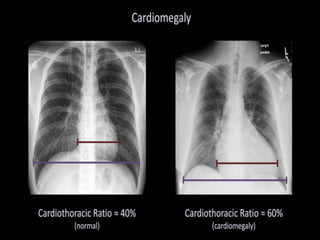

This document provides an overview of interpreting chest x-rays and identifies several key factors. It discusses the importance of inspiration, penetration, and rotation in obtaining a technically quality radiograph. It also outlines different views of chest x-rays including PA, AP, and lateral views. Finally, it identifies several anatomical structures that should be evaluated when interpreting a chest x-ray such as the lungs, heart, diaphragm, bones, and soft tissues.